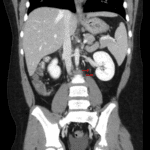

- Duplicated left renal collection system with volume loss and scarring in the upper pole

- No hydronephrosis

Duplicated left renal collecting system without hydronephrosis. Scarring in the left upper pole likely relates to reflux nephropathy.